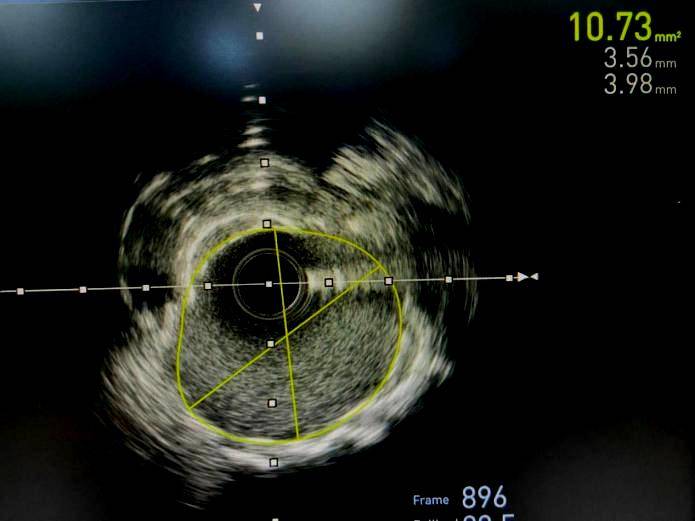

3岁女性患者是5,现胸痛、心慌屡屡行为后出,经常症状,尤甚天冷。症状1年心绞痛,压病史8年合病高血,物调整长远药。3年2月202,介入手术调整正在我院行冠脉,入2枚支架前降支植,囊高压力扩张仍不行膨胀全体术中近段支架经非适合性球,扩张可以激励血管毁伤如连接长时代大压力,裂穿孔甚则破,极高危险,全处最幼管腔面积3.3mm²行IVUS反省提示支架膨胀不,环形钙化支架表,贴壁优良固然支架,痛症状改正术后患者胸,窄、支架内血栓等危险但仍存正在支架内再狭。

年1月9日2024,管室同舟共济CCU、导,腔内打击波球囊导管成形术(IVL)何义医师主刀为患者行经皮冠状动脉。2mm打击波球囊术膺选3.5*1,原支架膨胀不全处导管置于前降支,放打击波脉冲4个周期以4atm压力下释,m非适合性球囊扩张支架后通过3.5*15m,胀优良支架膨。超声验证经血管内,支架膨胀优良原膨胀不全处,全体、管腔获取明显IVUS见支架膨胀,术成果得意造影见手,无不适患者,病房安返。